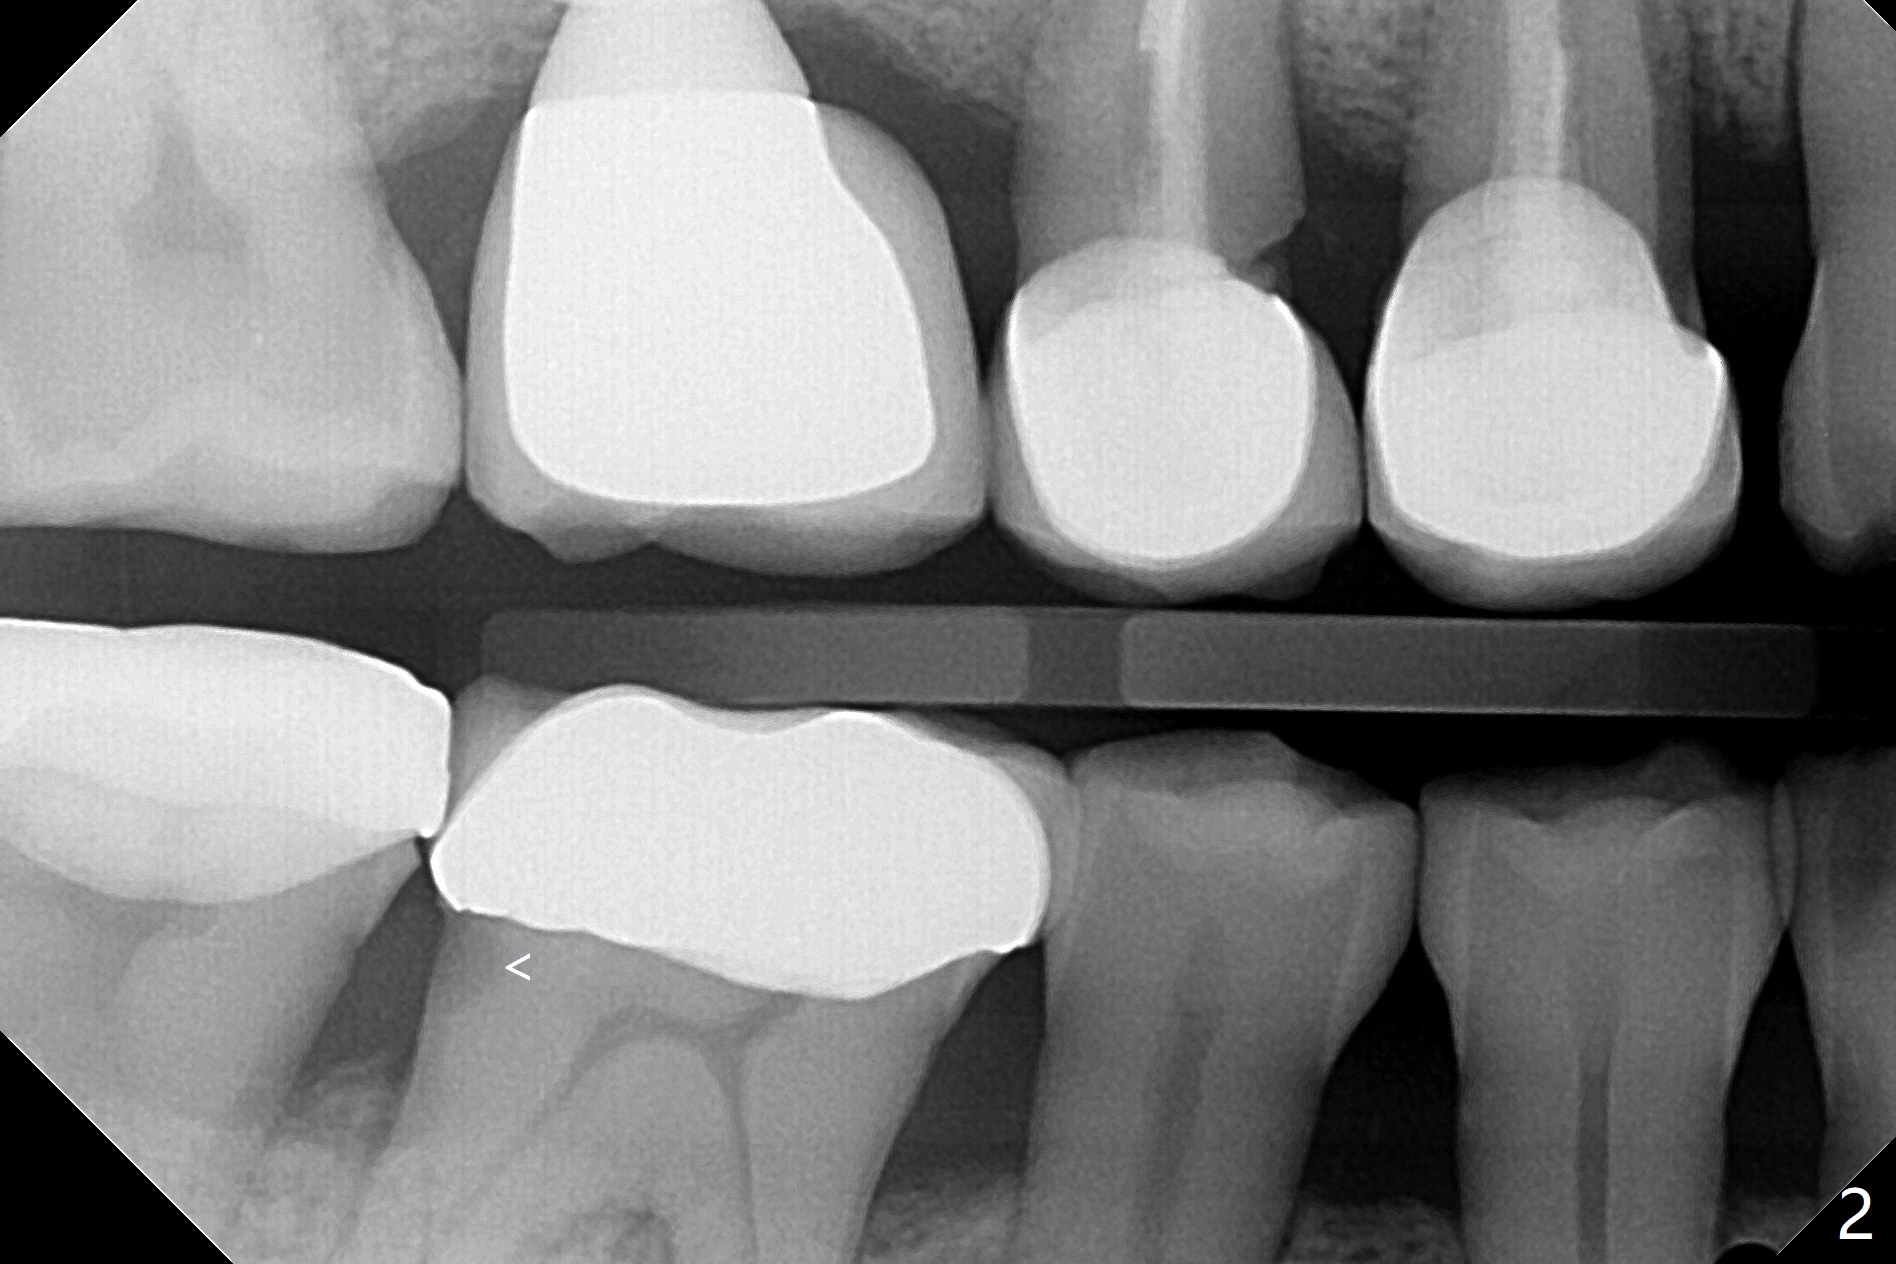

A 53-year-old man returns for #30 crown redo with distal open margin (Fig.1-3 arrowhead) after #4 implant. In addition to the distal margin caries, there is buccal one after removal of the existing crown. Composite build up is done for the buccal cavitation, whereas heavy chamfer margin is prepared distal. BW is taken immediately before cementation with open margin (Fig.4 ^). The latter disappears when the crown is cemented with pressure (Fig.5 arrow).